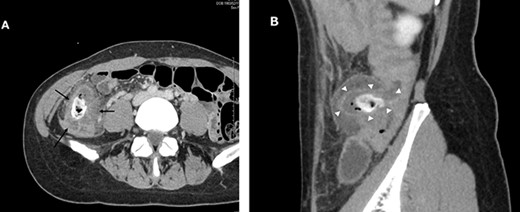

A 38-year-old woman presented with lower right abdominal pain of 3 days duration before the consultation. She had a history of left ovarian cystectomy and no history of medication use or allergies. She was 172-cm tall and weighed 59.0 kg. On examination, there was right lower abdominal pain with no rebound tenderness. The white blood cell count was 13 600 /μl, and the C-reactive protein was 3.8 mg/dl. Contrast-enhanced computed tomography (CT) revealed a 4-cm cecal diverticulum with inflammation and a fecalith (Fig. 1). An abscess penetrated through the mesenteric side and was localized in the mesentery. The diagnosis was cecal colonic diverticulitis and classified as Hinchey II. The abdominal symptoms were localized; hence, the patient was treated with antibiotics. From Day 1 of hospitalization, she was on nil per oral and administered CMZ at 3 g/day. On hospitalization Day 3, the right lower abdominal pain improved, and contrast-enhanced CT imaging was performed. The cecal colonic diverticulitis improved, and the fecaliths migrated to the transverse colon (Fig. 2). Moreover, the inflammatory reaction improved. In a multidisciplinary meeting, we discussed that the patient should undergo a detailed examination, including colonoscopy, and elective surgery after readmission. However, we suggested that surgical treatment should be performed as early as possible after considering the risk of early recurrence and bleeding. The patient wished to undergo minimally invasive surgery; thus, we performed an immediate ileocolectomy and lymphadenectomy using SILS as we did not rule out the likelihood of malignant disease.

Abdominal and pelvic CT on hospitalization Day 3. Axial images (A and B) showing improved cecal colon diverticulitis (black arrows); however, fecaliths migrated to the transverse colon (white arrowheads).